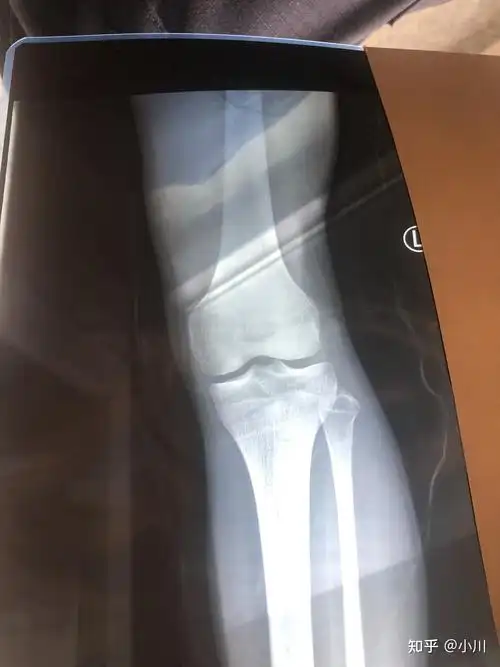

骨骺线闭合了为什么还在涨? - 知乎